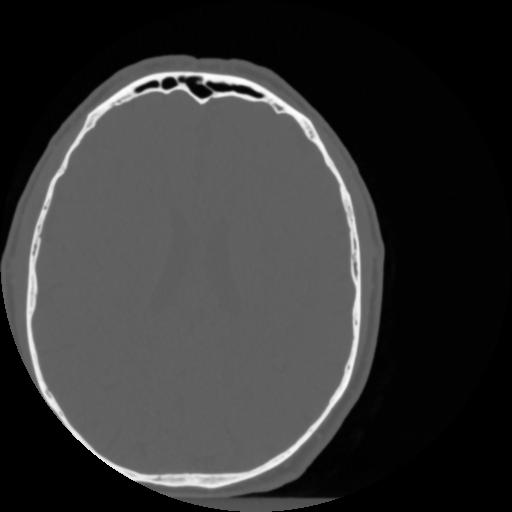

4 CEREBRO,,Vol,0.5,CEREBRO,,